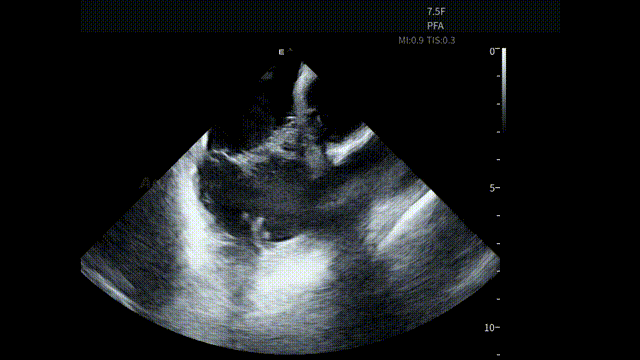

手术开始后,AgileView™ ICE 导管作为术中影像辅助工具,经股静脉穿刺进入心房。考虑到本台手术将搭配PulseSelect™消融导管使用,助手将ICE主机调整至“PFA预设模式”,便于后续更直观的判断导管贴靠情况。通过 HomeView 视角,术者首先了解了患者心腔整体结构,为操作提供统一的影像参考。

HomeView

随后,ICE对左心房、左心耳及心包区域进行系统性扫查。术前重点评估左心耳内是否存在血栓形成,并同步观察心包情况,确保在消融前,关键风险已被充分排查,为保证手术安全提供直观依据。

术前心包